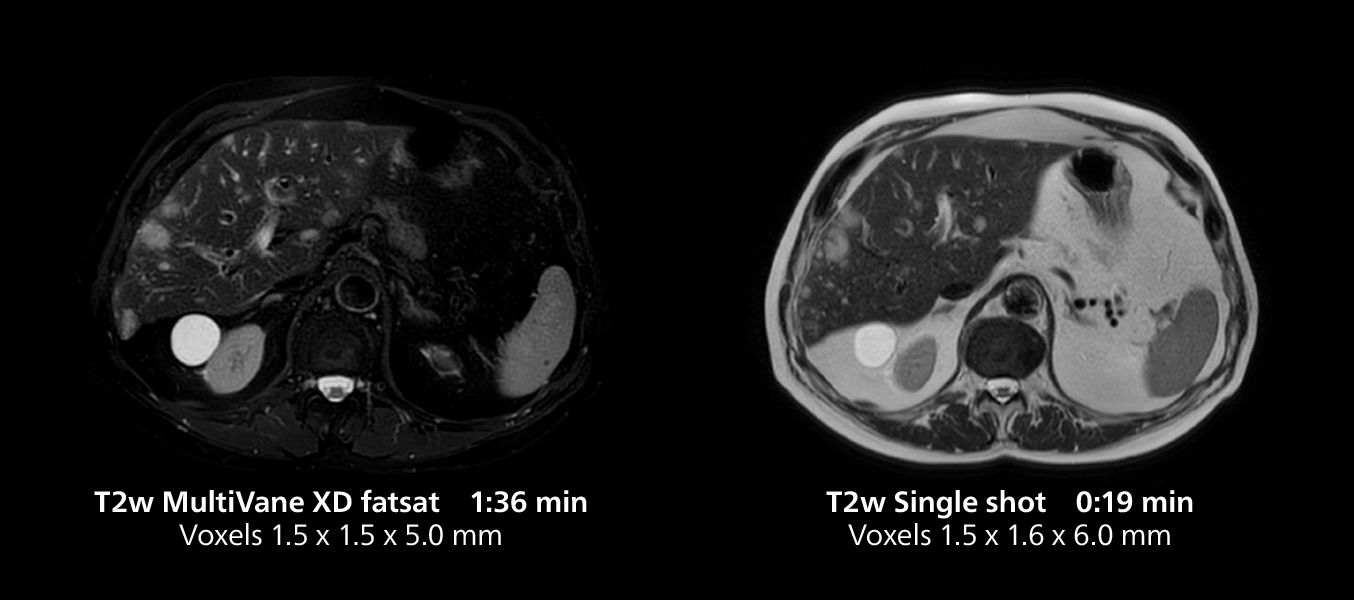

Liver imaging using MR 5300

This case includes 3D free breathing and 4D dynamic free breathing MRI of a metastasized liver. A high quality fatsat sequence with good resolution is obtained in 1:36 minutes with T2-weighted MultiVane XD.

Liver imaging using MR 5300

This case includes 3D free breathing and 4D dynamic free breathing MRI of a metastasized liver. A high quality fatsat sequence with good resolution is obtained in 1:36 minutes with T2-weighted MultiVane XD.